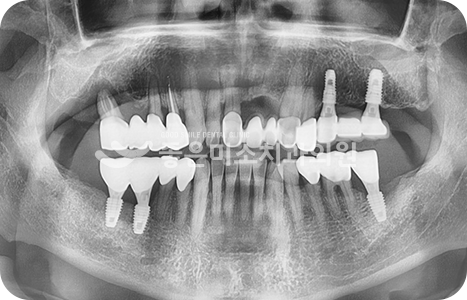

• 좋은미소 코멘트

어금니 상실로 앞니까지 안좋아지신 케이스입니다.

전치부의 심미와 구치부의 기능을 동시에 회복하기 위해

전체적으로 임플란트 식립하였습니다.

before

after